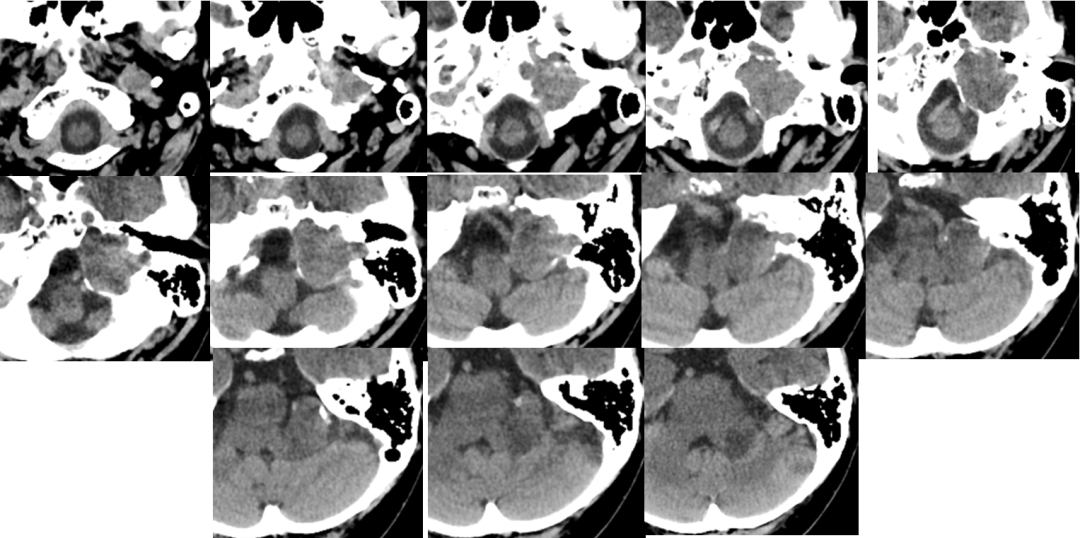

术后影像

![]()